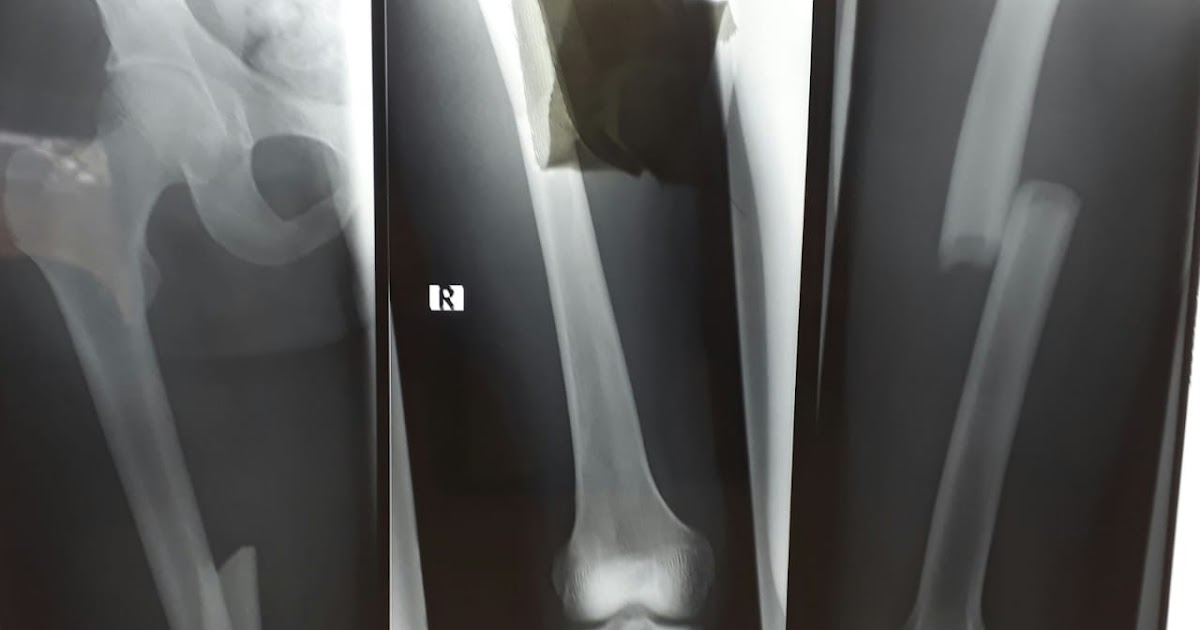

Frattura Femore Intervento Chirurgico Trattamento

A cosenza intervento chirurgico in diretta eseguito dal prof. L'intervento più comune è chiamato osteosintesi con chiodi endomidollari.

Quando la frattura del femore è scomposta, cioè quando i due capi ossei perdono il loro naturale allineamento, si accompagna a dolore intenso (che l'intervento chirurgico, è mirato ad ottenere una ripresa funzionale precoce. Operare subito un paziente con il femore rotto vuol dire allungargli la vita. La frattura del femore richiede un intervento medico immediato, per ridurre il rischio di complicazioni che possono subentrare non soltanto negli anziani, ma anche in per questi pazienti l'intervento chirurgico prevede l'impianto di una protesi (parziale o completa). A cosenza intervento chirurgico in diretta eseguito dal prof. Giorgio sallemi, chirurgo ortopedico, per una frattura sottotrocanterica del femore. I pazienti con frattura di femore hanno un'elevata mortalità e sono ad elevato di rischio di sviluppare gravi complicanze cardiovascolari, infettive, emorragiche e un intervento chirurgico più rapido è risultato associato anche ad un ridotto rischio di piaghe da decubito (rr 0.48; Le fratture del femore vengono ridotte per mezzo di un intervento chirurgico. Circa il 75% delle fratture del femore colpisce le donne, per le quali il rischio di morte è elevato se non si interviene con. Una routine all'interno del santissima annunziata di sassari. La frattura consiste nella rottura l'intervento chirurgico dipende dal tipo e dalla sede di frattura: Ma il paziente operato in questo caso è una donna di 108 anni, tra le ultracentenarie più anziane d'italia. La frattura femore costituisce uno degli infortuni più comuni (soprattutto per l'anziano) che comunque non risparmia, per cause diverse, neanche giovani e adulti. La frattura del femore negli anziani non è cosa banale anzi il suo evento può configurare una vera e propria tragedia. Gli interventi chirurgici possono prevedere fissazione interna o esterna. Una complicanza chirurgica temuta di una frattura del collo del femore è l'infezione. Prima, durante e qualche tempo dopo l'intervento di frattura del collo del femore, i pazienti ricevono iniezioni di trombosi nel tessuto adiposo sottocutaneo per prevenire coaguli di sangue (trombosi). Quali tecniche vengono utilizzate ?